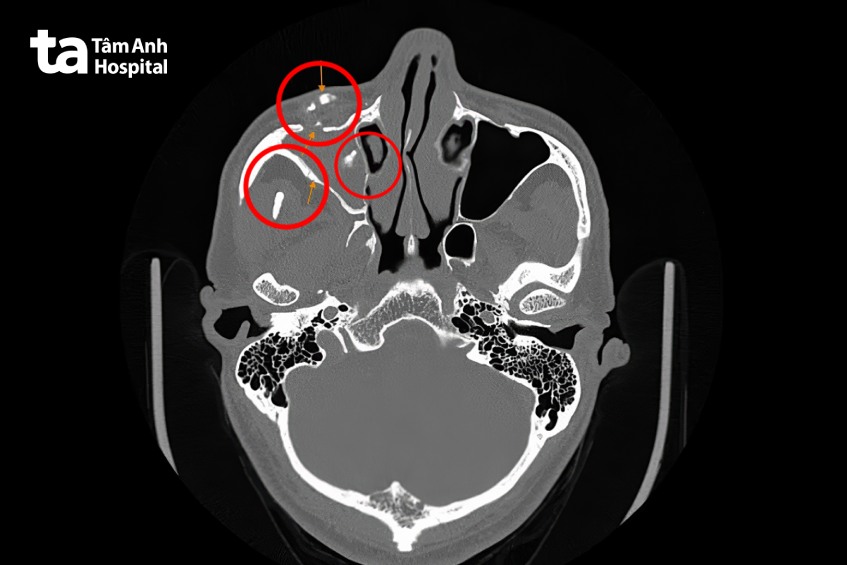

Kết quả chụp CT cũng ghi nhận, cấu trúc đậm độ cao trong mô mềm vùng má phải, kèm vài nốt vôi nhỏ xung quanh và phù nề mô mềm quanh vị trí này.

GS.TS.BS Trần Phan Chung Thủy, Cố vấn Trung tâm Tai Mũi Họng, Bệnh viện Đa khoa Tâm Anh TP.HCM chẩn đoán ông T. viêm đa xoang nhầy mủ, dị vật phần mềm vùng má và dị vật xoang hàm.

GS Chung Thủy giải thích, dị vật này là một vật thể nhỏ nằm trong mô mềm ở má phải. Ngoài ra, xung quanh xoang hàm phải còn xuất hiện một số nốt cản quang giống kim loại, sưng viêm, phù nề – dấu hiệu của phản ứng lâu dài của cơ thể với dị vật. Xoang hàm là các hốc xoang nằm ở hai bên gò má và hốc mắt. Tình trạng viêm xoang hàm đã lan rộng, ứ dịch và phù nề mô mềm nên gây sưng mắt, sưng mặt.

GS Chung Thủy xác định dị vật ở vùng má và mặt trước xoang hàm phải, gần hốc mắt và tiến hành phẫu thuật lấy các dị vật. Khi tiếp cận vùng dị vật, thấy mô viêm lan rộng, ổ mủ và áp-xe bao quanh dị vật. GS Chung Thủy lấy ra các mô viêm, dịch mủ, ổ áp-xe và bao xơ bao quanh dị vật. Việc lấy mô viêm cùng dị vật giúp loại bỏ hoàn toàn tổn thương.